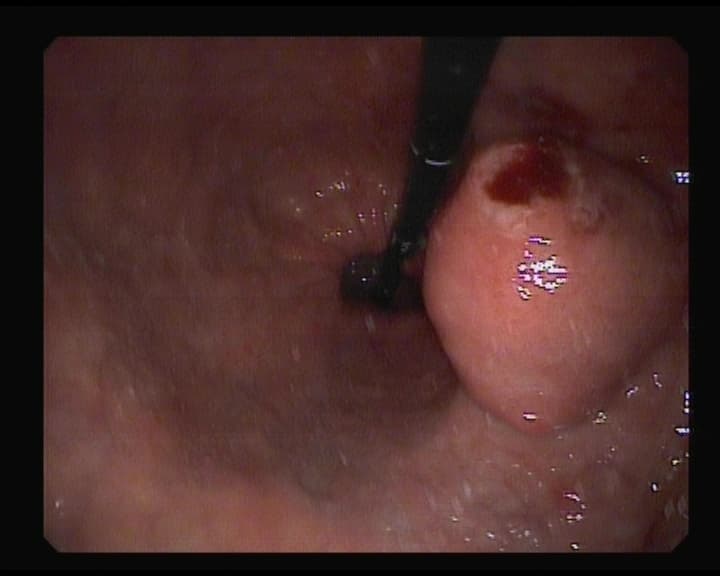

Hemorragia digestiva alta.

Punto sangrante en Duodeno, solucionado con colocación de un clips metálico,